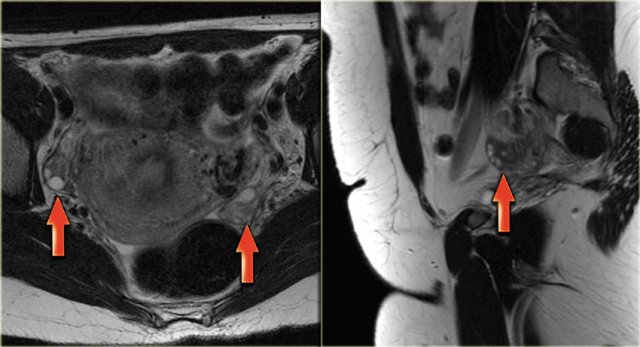

Endometrioid ovarian carcinoma

On ultrasound both ovaries are markedly enlarged and contain cystic components with intracystic solid components (arrows).

The complex solid-cystic lesions, in addition to being bilateral, are suspicious for a cystic ovarian neoplasm and warrant further evaluation.

Again, the role of imaging is to confirm a lesion is present and to decide that this is not a lesion that can be classified as definitely benign nor a lesion that can be safely followed-up: action is required.